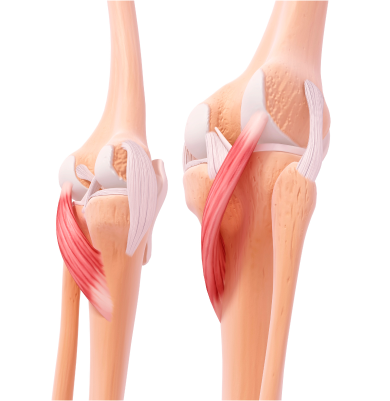

무릎 인대 손상

외부 충격이나 과도한 움직임으로 인해 무릎 관절의 인대가 늘어나거나 찢어지는 질환

주요원인

주로 스포츠 활동 중 갑작스러운 방향 전환, 점프 착지, 외부 충격 등으로 발생합니다. 일상생활 중 무릎을 비트는 동작이나 넘어짐 등도 원인이 될 수 있습니다.

주요증상

• 부기와 압통이 생기고 무릎을 움직이기 어렵습니다.

• 걷거나 체중을 실을 때 무릎에 불안정함을 느낄 수 있습니다.

• 손상 정도에 따라 관절의 움직임 제한 및 관절 불안정성이 동반됩니다.